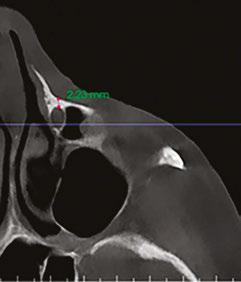

A recent 2025 retrospective review by Holtzclaw, et al.,11 evaluated anonymized cone beam computer tomography (CBCT) scans from 300 sequential referrals using PLACATE guidelines to determine transnasal dental implant feasibility. In this study, inferior conchae were initially located in the coronal plane, and imaging crosshairs were positioned just superior to this structure in the axial plane. To evaluate the ipsilateral and contralateral transnasal engagement points, imaging crosshairs were next positioned over each concha in the sagittal plane. This prelacrimal engagement point, sometimes referred to as the “Z-Point”,6,12 was then evaluated according to PLACATE guidelines as follows:

1. Simmen classification19 determined by measurement from the external aspect of the frontal maxilla to the most anterior aspect of the nasolacrimal canal (Figure 5)

2. Mediolateral measurement of prelacrimal bone width (Figure 6)

3. Vertical measurement of subnasal bone height

4. Vertical measurement from subnasal bone to prelacrimal bone engagement point (Figure 7)

The results of this study found that only 30.54% of patients qualified for transnasal dental implants anatomically. The most common disqualification was inadequate prelacrimal bone width which affected 49.71% of patients. Excessive subnasal bone height, which could foster placement of conventional dental implants, eliminated 28.74% of patients. The third most common reason for patient disqualification from transnasal dental implant placement, 22.16% of patients, was Simmen 1 classification which would result in potential violation of the nasolacrimal canal.